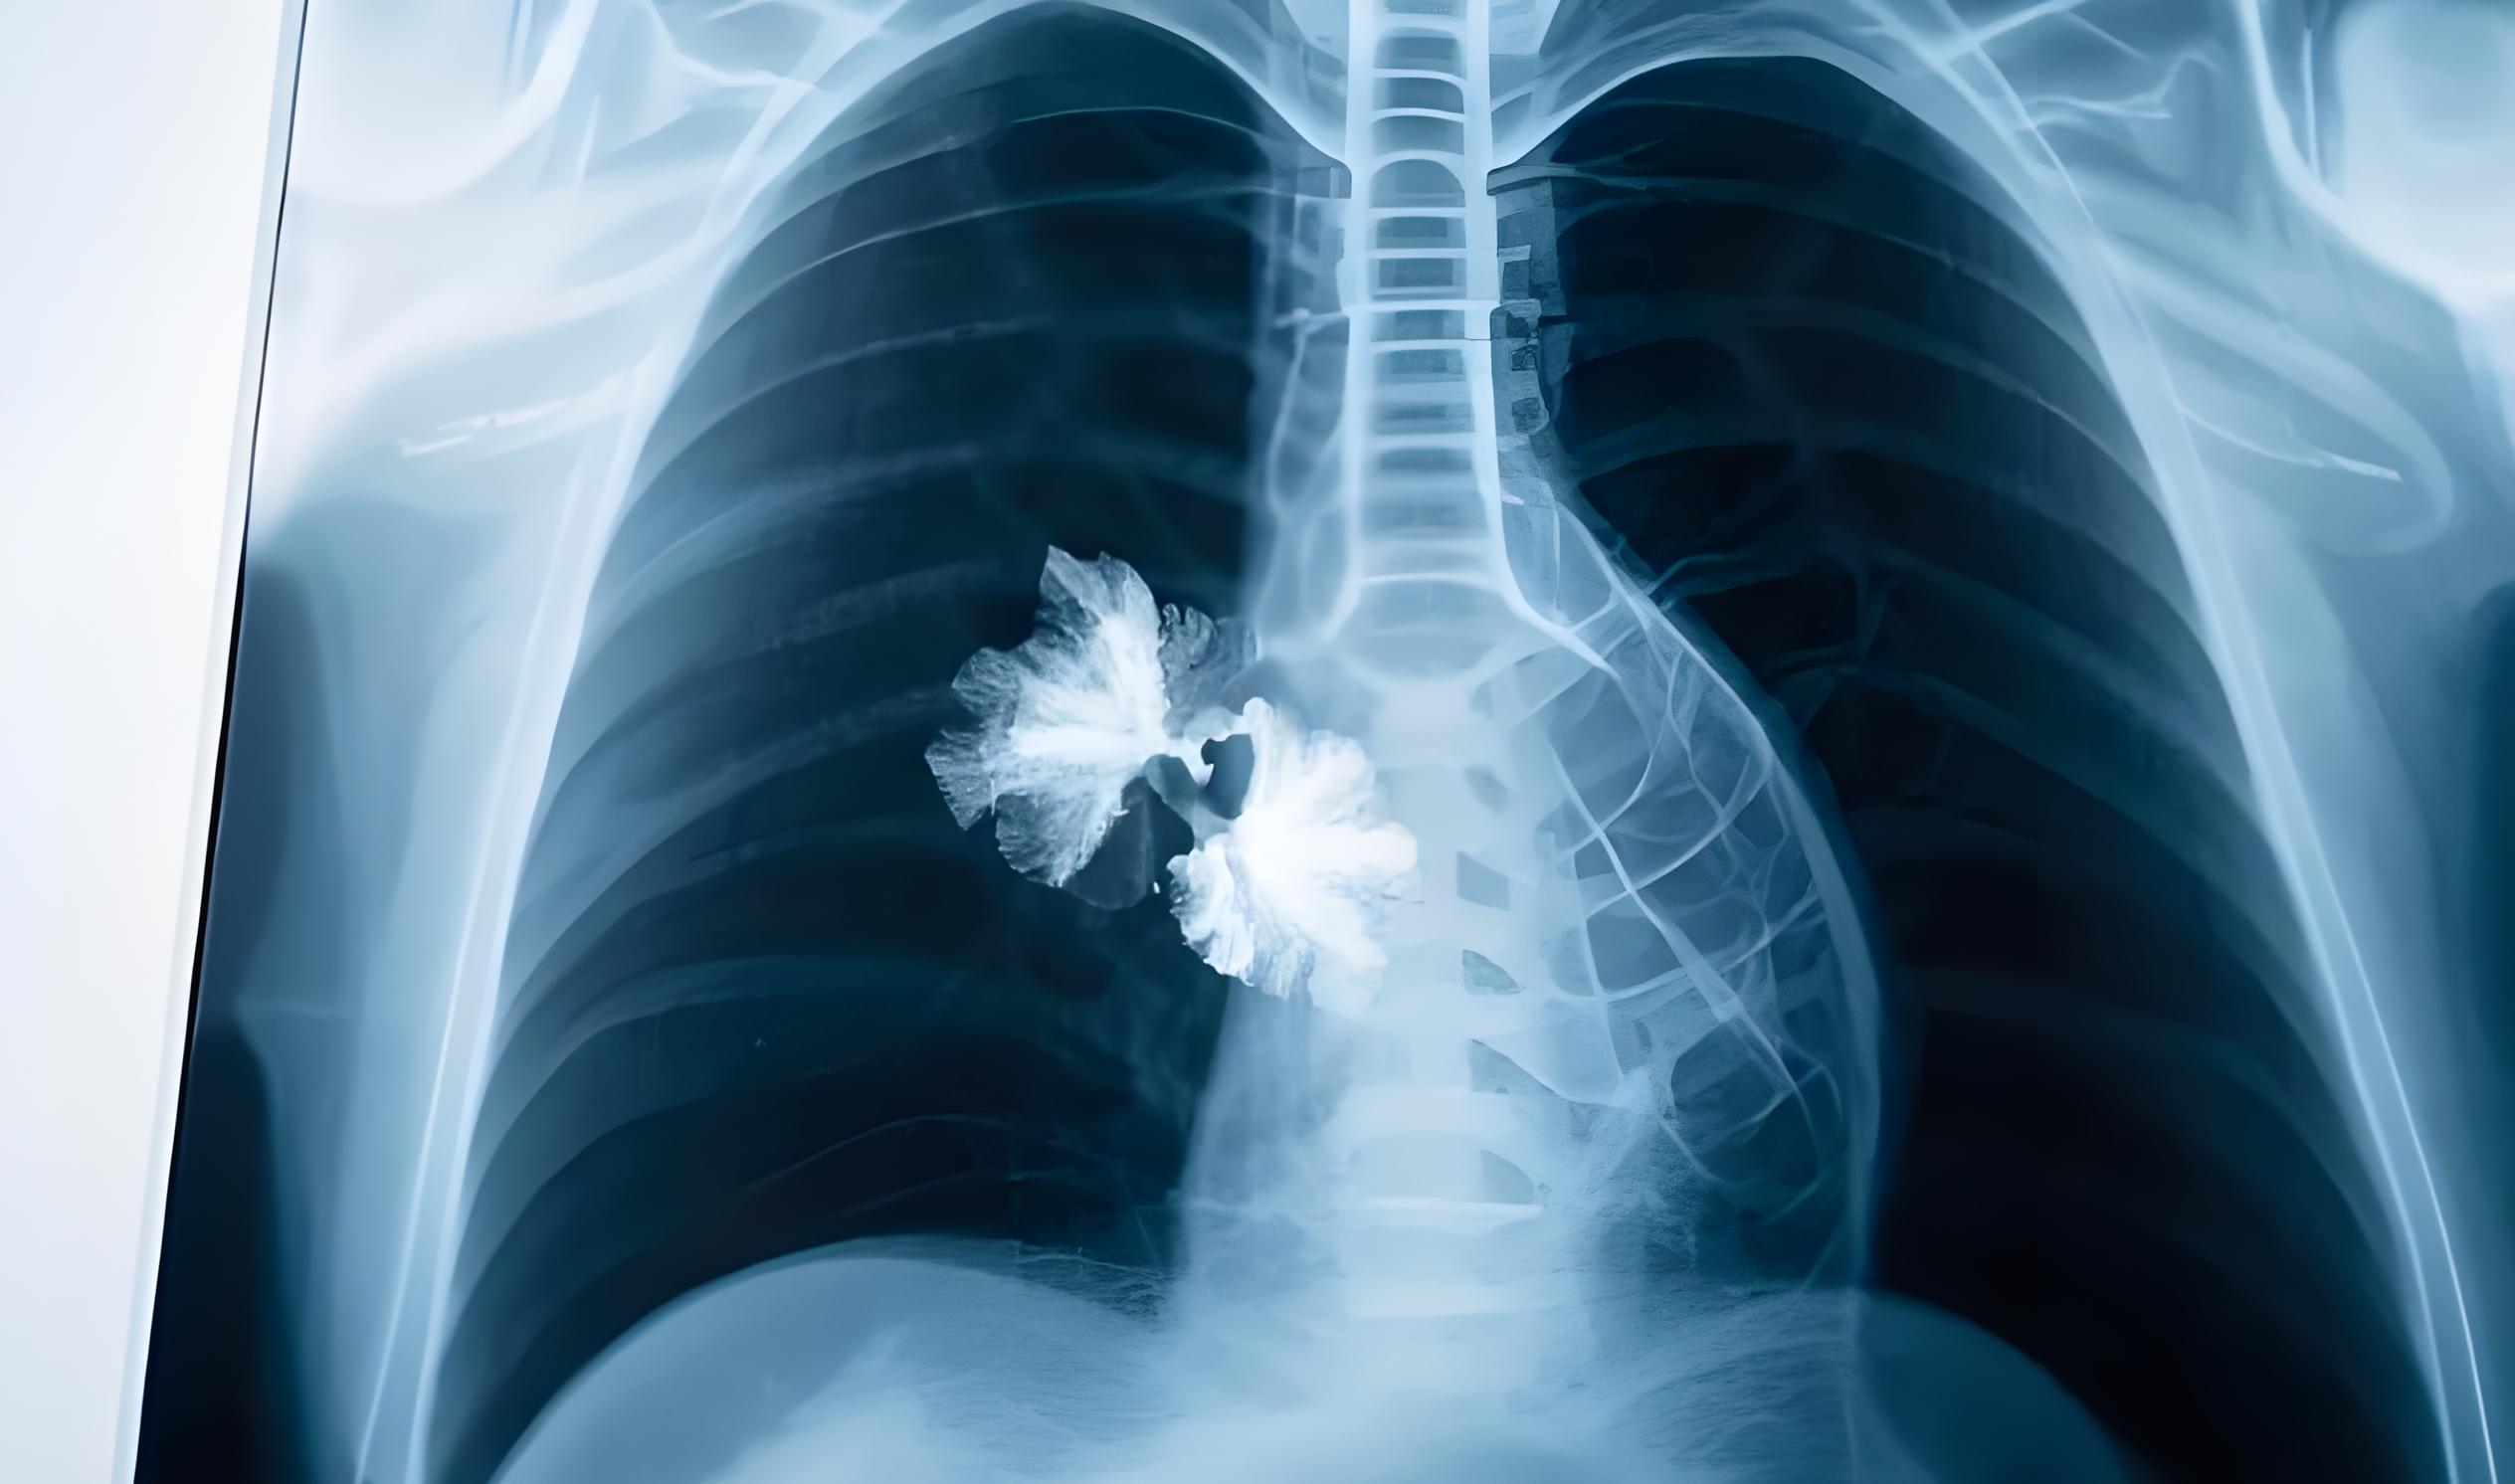

近年來,肺結節問題愈發嚴峻,已成為全球矚目的公共健康難題。

據《Cell》雜志最新權威研究,全球肺結節患者人數增長超60%。《健康概覽》報告顯示,截至2024年3月,全球患病人數超15億,中國就有5.2億。

《國民健康白皮書(2024版)》指出,我國肺結節檢出率達55.9%,近乎每十人中就有六人面臨此健康風險,后疫情時代,肺結節的威脅不容小覷。